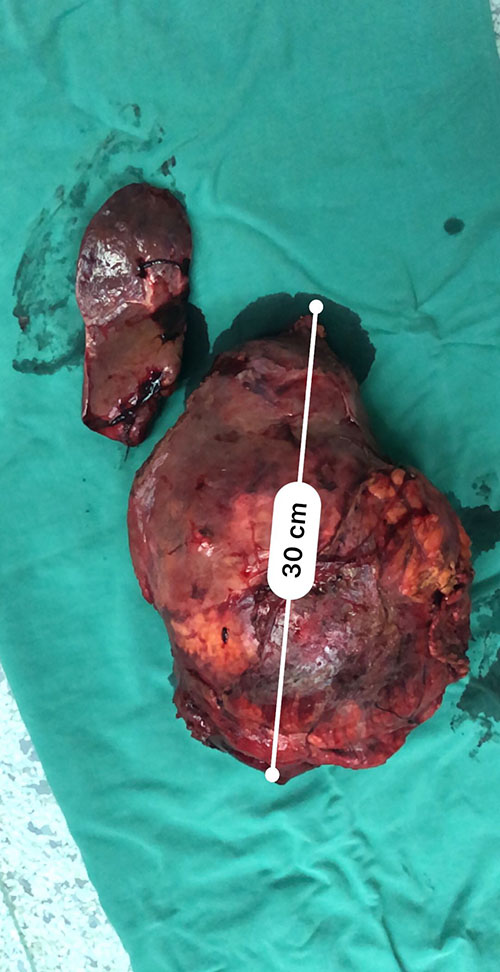

左肝巨大肝癌--左肝巨大肝癌切除